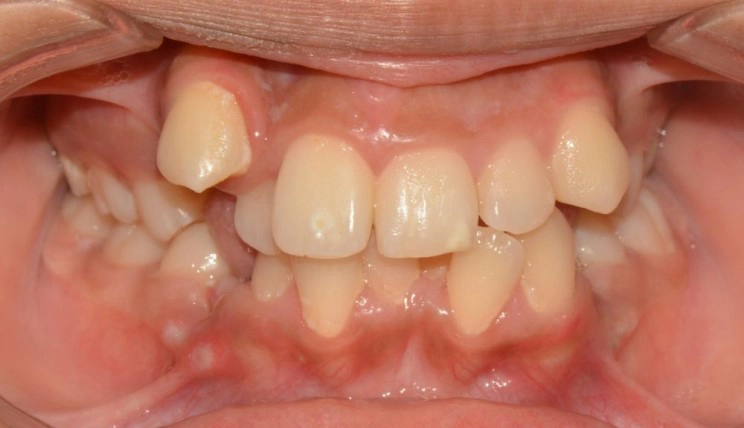

Crowding

Crowding is the condition in which there is a discrepancy between tooth size and space available for the teeth to be aligned in the dental arch

Patient Information:

Age: 17

Gender: female

Invisalign Treatment Option: Invisalign Comprehensive

Total Treatment Time:

29 months